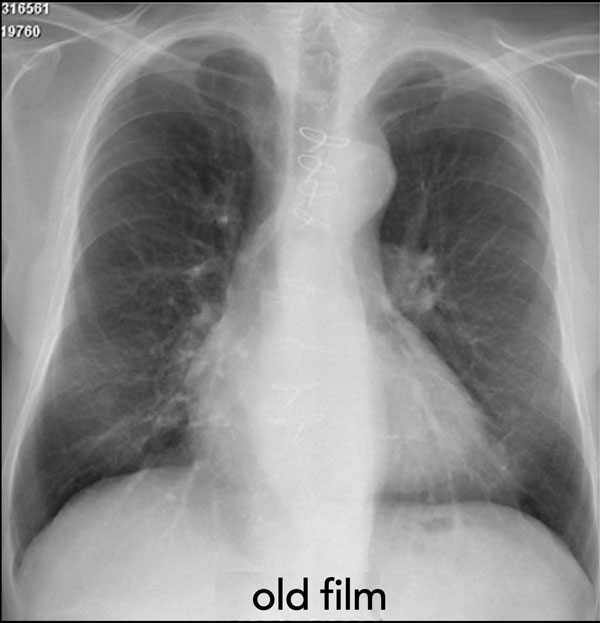

Tầm quan trọng của Hình ảnh Cũ

Luôn luôn so sánh phim X-quang ngực hiện tại với các phim cũ trước đó—đây là nguyên tắc cơ bản trong đọc phim chẩn đoán hình ảnh.

Thực tế, người ta thường nói rằng “phim quan trọng nhất chính là phim cũ”, vì nó cung cấp bối cảnh thiết yếu để đánh giá sự ổn định hoặc tiến triển của các tổn thương.

Ví dụ, một khối ở phổi không thay đổi trong nhiều năm thì khó có khả năng là ung thư phổi nguyên phát.

Ví dụ Lâm sàng: Dấu hiệu Kín đáo của Suy tim Sung huyết

Hãy bắt đầu bằng cách xem xét các phim X-quang ngực hiện tại.

Chỉ dựa trên các hình ảnh này, người đọc có thể nghi ngờ suy tim sung huyết (CHF), mặc dù các dấu hiệu còn khá kín đáo.

Bây giờ hãy xem lại phim cũ trước đó…

Việc cuộn qua lại giữa phim hiện tại và phim cũ giúp tăng đáng kể độ tin cậy trong chẩn đoán suy tim sung huyết.

Các dấu hiệu so sánh chính bao gồm:

- Kích thước tim: Tăng nhẹ so với phim trước; tuy nhiên, tim to đã hiện diện từ trước.

- Hệ mạch máu phổi: Cương tụ mạch máu nhẹ gợi ý tăng áp lực tĩnh mạch phổi.

- Hình ảnh mô kẽ: Dấu hiệu kín đáo của phù mô kẽ.

- Tràn dịch màng phổi: Tràn dịch lượng ít hai bên, với thay đổi kín đáo ở bờ dưới-sau của các thùy dưới, gợi ý tích tụ dịch.